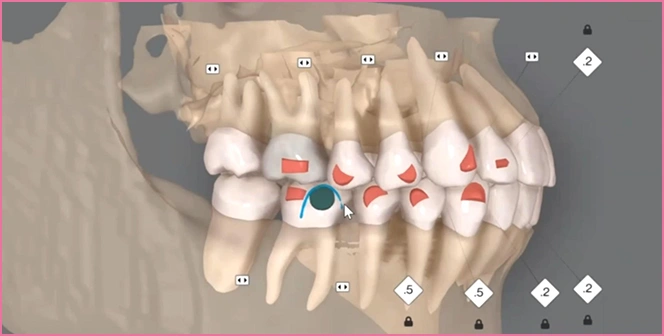

AI任せにしない、0.1mm単位の

オーダーメイド

オーダーメイド設計のイメージ

多くの医院では、AI(人工知能)が算出した治療計画をそのまま使用しますが、 歯の動きには個人差があり、計画通りに進まないこともあります。

そのまま修正を重ねると、マウスピースの枚数が増え、 治療期間が長引くケースも少なくありません。

同じ歯並びでも、計画をどのように調整・設計し直すかによって、矯正の期間だけでなく、成功するかどうかも変わります。

iiTeroスキャナーで取得した高精度な歯型データを、セファログラムと組み合わせて解析。

歯・骨格・お顔のバランスを統合した3Dモデル上で、矯正後の歯並びやフェイスラインの変化まで確認できるため、治療のイメージをより可視化できます。

3Dデータをもとに、治療後までの変化を画面で確認できます。

よくあるAIの自動設計データをそのまま使うのではな く、当院では担当医が1本ずつ歯の動きを細かく調整 し、噛み合わせまで含めて仕上がりの精度を高めます。 完成後は、歯がどう動くか/期間を一緒に確認してか ら治療を進めます。